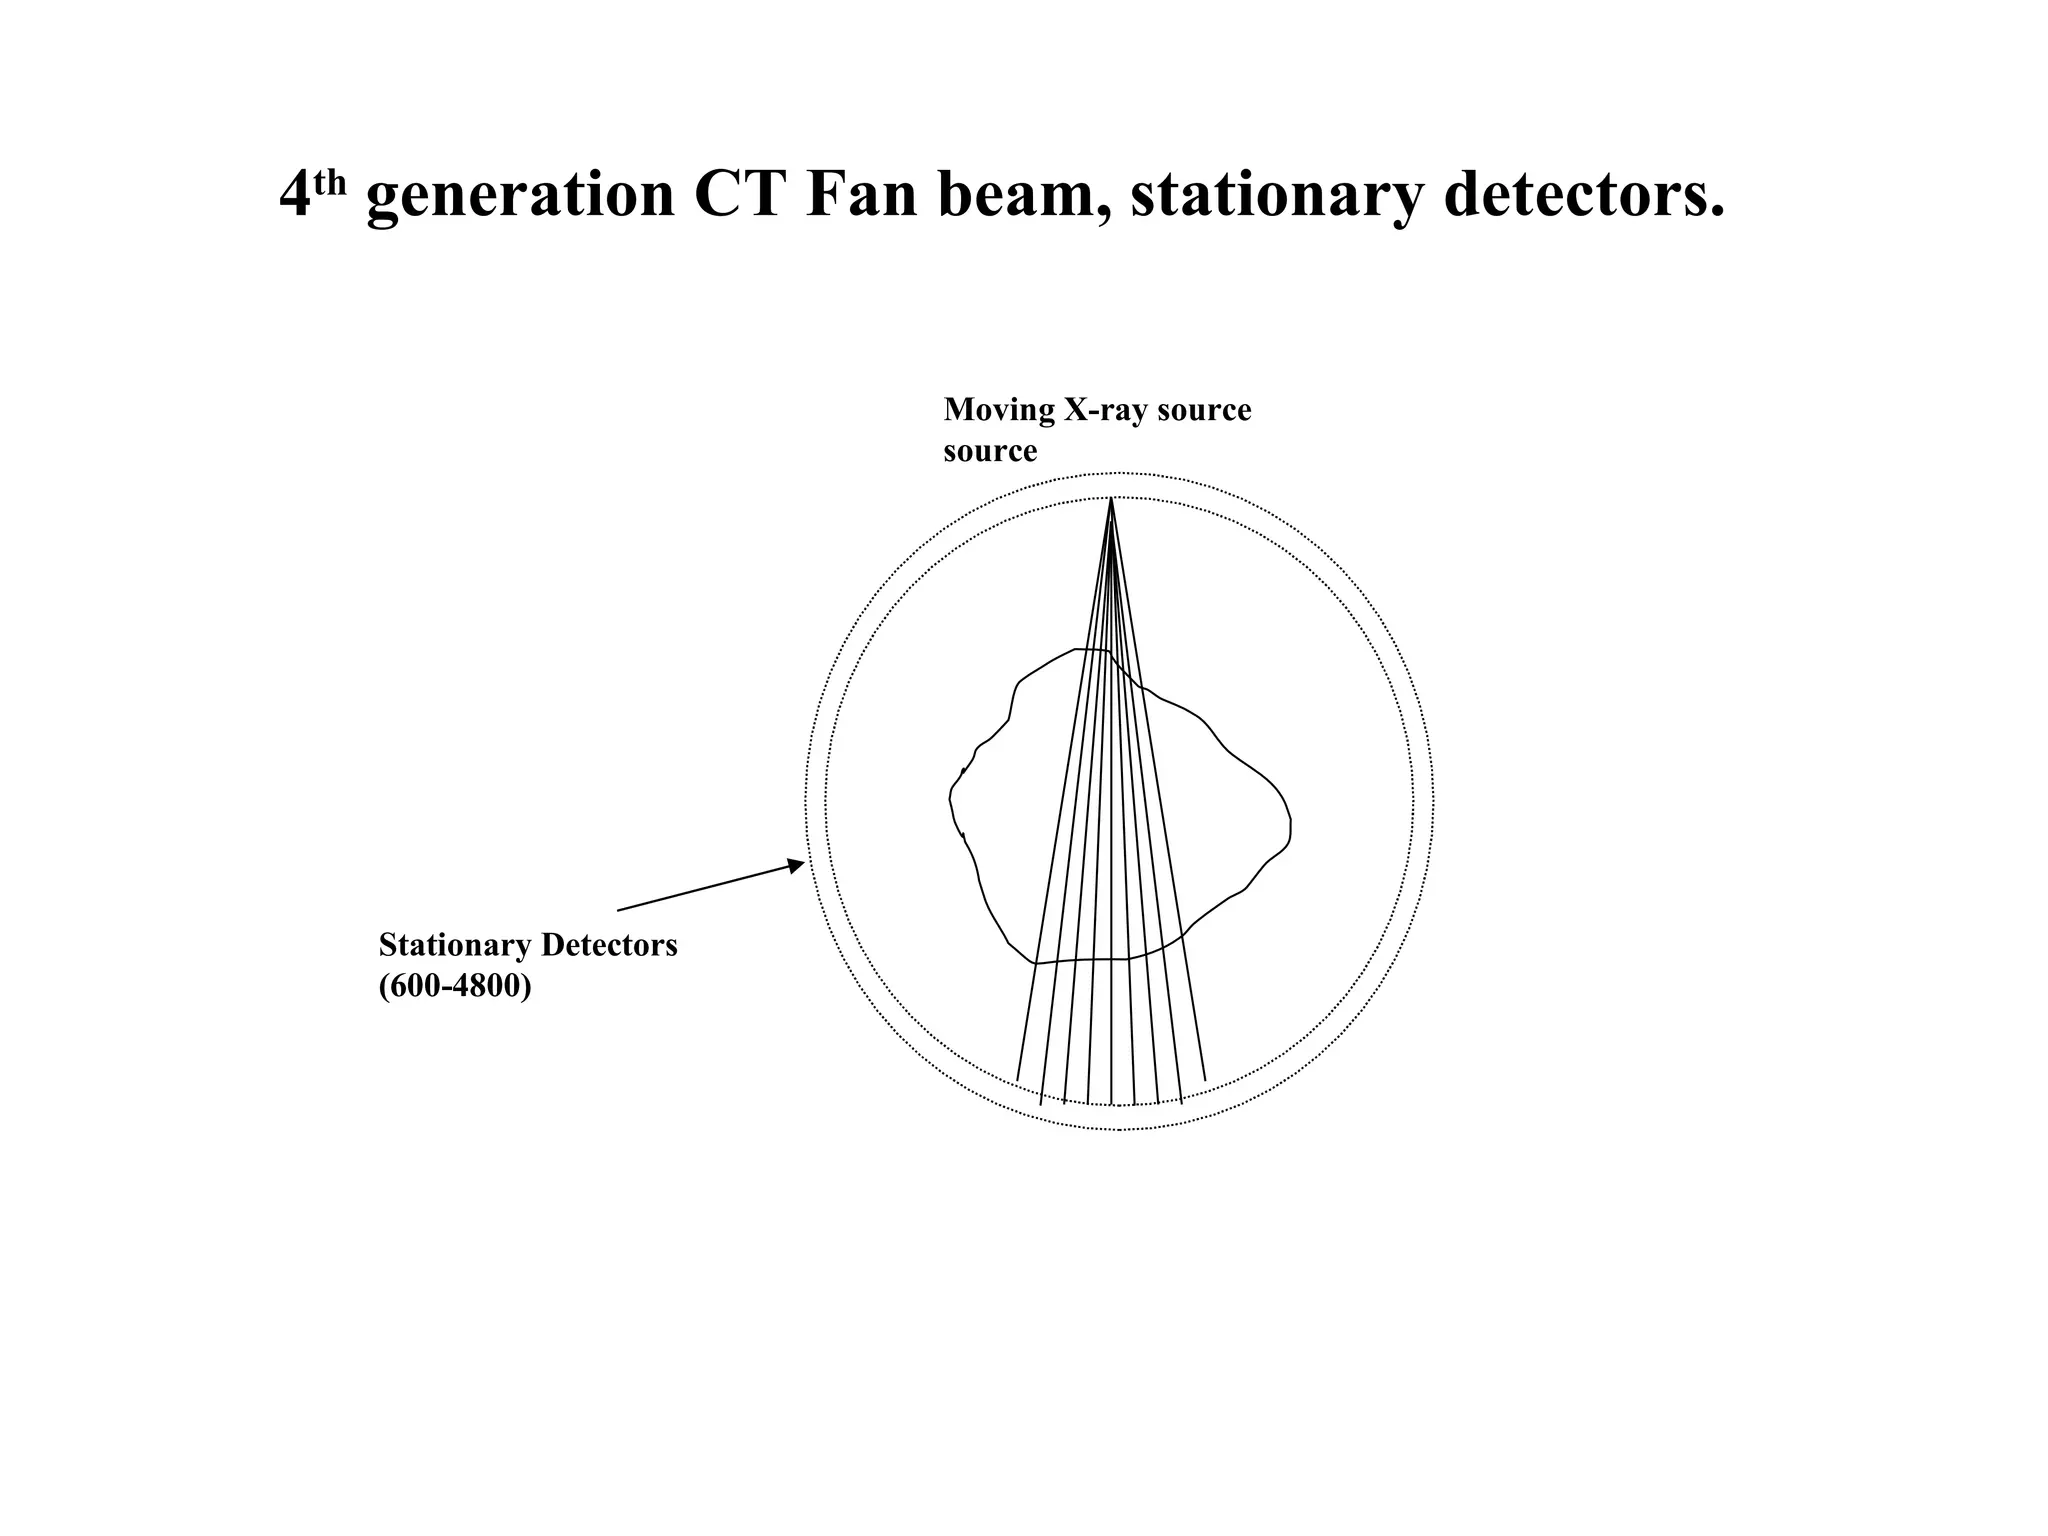

The document discusses various medical imaging modalities including x-rays, computed tomography (CT), and digital mammography. It describes the basic principles and historical development of these technologies, how images are formed, and what types of anatomical features and abnormalities they can detect. Key advances include the development of digital systems that allow image manipulation and remote consultation. While promising, digital mammography still faces challenges around resolution and cost.